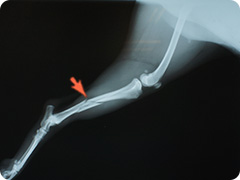

- 骨折

- 高いところから飛び降りたりすることで骨折することがあります。骨折した足はぶらーんとして床に足を付けられない状態になります。

創外固定法による治療

プレートを用いた治療